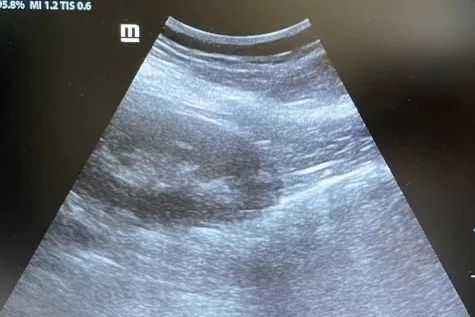

腹腔镜下肾穿刺后肾周无明显血肿

肾病二科团队联合泌尿中心团队为两位患者制定了详细的手术方案。在麻醉科、门诊手术室和病理科的大力配合下,手术团队顺利从患者的后腹膜插入腔镜、穿刺一次成功,从肾脏内取得了诊断所需肾组织并送检病理检查,在内镜可视情况下观察并及时处理了术中出血情况。两位患者的手术过程均平稳顺利,活检结果为他们的进一步治疗起到了显著作用。